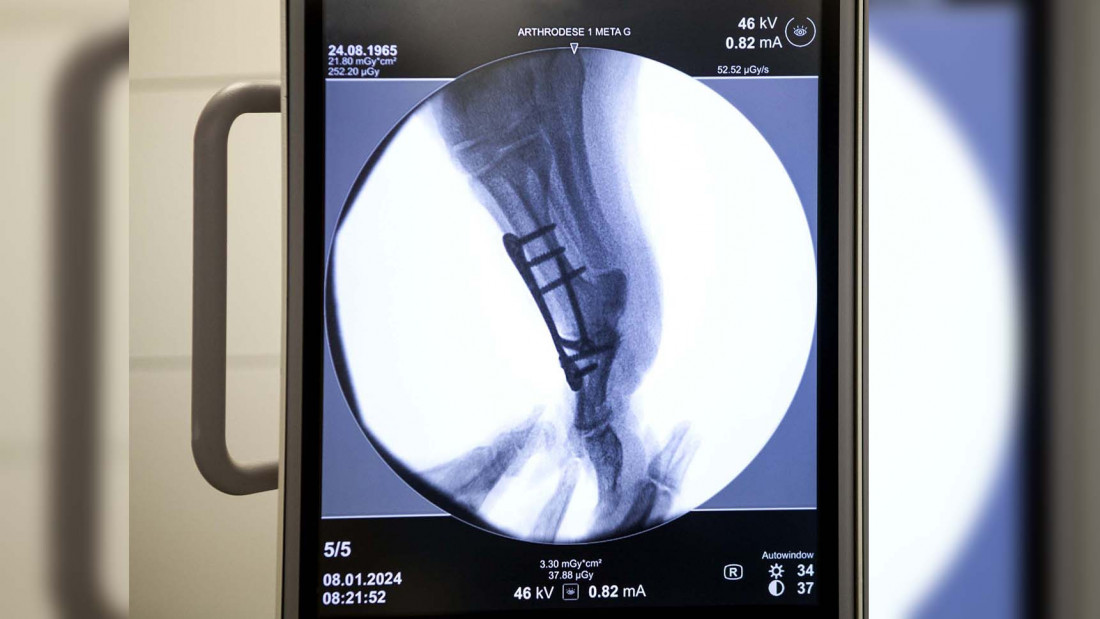

U najvećoj ortopedskoj ustanovi u regionu, Institutu za ortopediju Banjica, od ukupno deset operacionih sala, za ugradnju kuka i kolena svakodnevno se koristi pet do šest njih.

Direktor Instituta za ortopediju "Banjica" Zoran Baščarević kaže da su prošle godine obavili oko 4.500 operacija veštačkih zglobova.